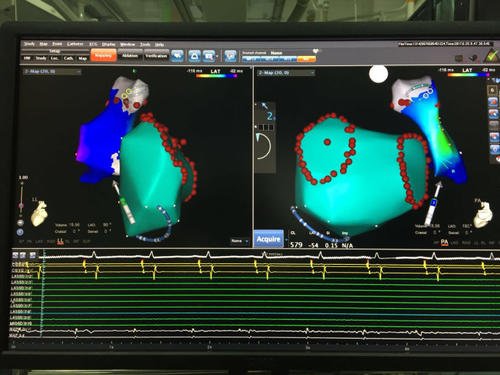

李海鹰主任是全国电生理专家,在电生理方面有很深的造诣,在心律失常及冠心病的诊治有丰富的经验,电生理及冠脉造影均为微创检查,对正常人来说并不会造成什么影响,但黄先生基本情况差,全身多器官功能不全,他能承受得了这些微创检查吗?另一方面,患者病因未除,病情随时可能进一步恶化,诱发恶性心律失常,患者会有很大的生命危险。情况进击,李海鹰主任决定尽快择期为患者进行相关检查,为了保证患者安全,李主任请了院内多个相关科室的专家会诊,一起商讨治疗方案,提高患者的耐受能力,再三斟酌之后,最后李主任决定先行电生理检查,尽可能帮助患者找到预激的“旁道”并关掉这条“旁道”,再行冠脉造影检查,但在这之前,还需要在密切关注下调整患者的身体状况,尽可能的恢复各脏器的功能。一切准备就绪,李主任带领团队于3月10日为患者行心内电生理检查,成功找到“旁道”,并予射频消融消除旁道,重复刺激,未见预激波,表明患者的预激“旁道”被李主任成功消除了!手术取得成功,黄先生亦无特殊不适,安返病房。